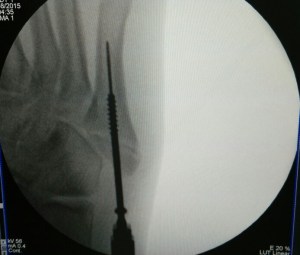

Percutaneous cannulated screw fixation of this displaced avulsion fracture of the 5th metatarsal base was performed.

This procedure is done via a small incision and guided by x-rays fluroscopy.